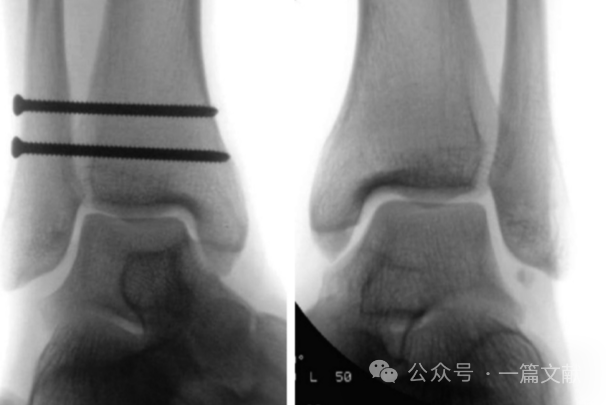

2,透视踝穴位时,夹持内固定后的腓骨向外、向后牵拉,并与健侧对比,观察是否存在关节间隙的增宽。如下图:

图片